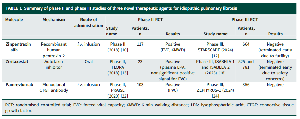

A lung cancer patient's prognosis is defined by a combination of the cancer stage, which defines the cancer location and spread; the patient's performance status, acting as an indirect measure of their ability to tolerate treatment; and finally, more intrinsic tumour-related properties such as the local immune contexture and tumour genetic makeup. The latter two dictate whether immunotherapy and targeted agents are treatment options.